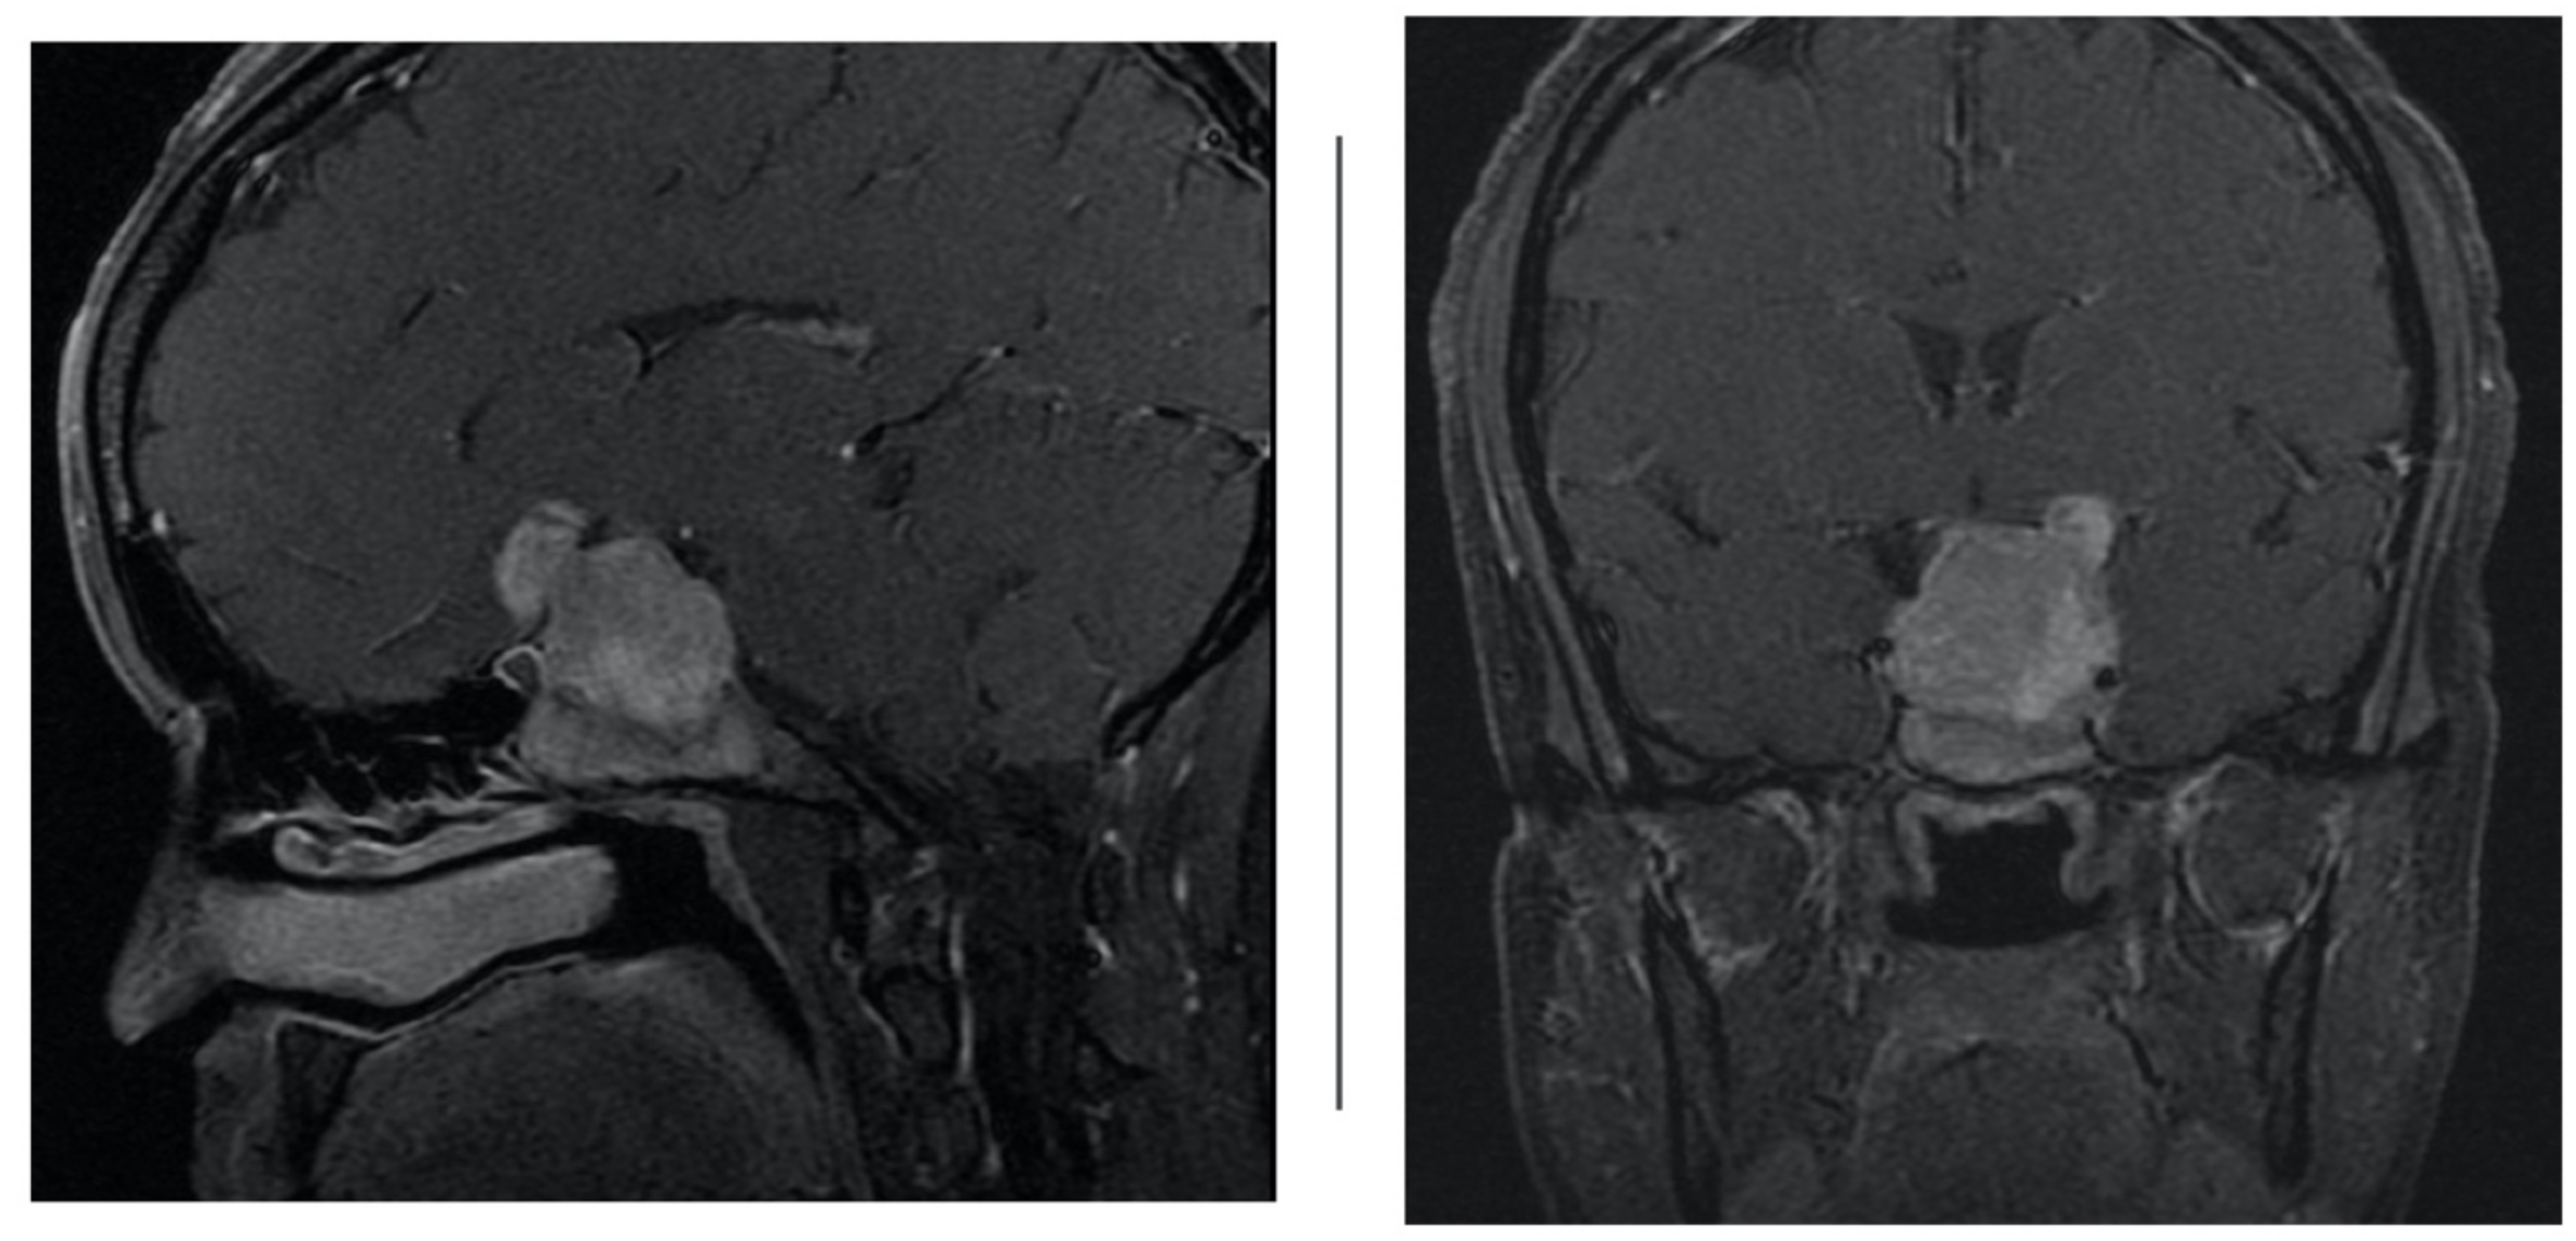

At our institution, four patients (n = 4) were assigned to acetazolamide therapy after they developed iatrogenic cerebrospinal fluid leak from transsphenoidal surgery for tumor resection from June 2018 to June 2019 by the senior neurosurgeon. Table 1 shows a summary of patient demographics. Average age was 42.5 years and average BMI was 31.6 (range 26.5–36.4). All four tumors were greater than 10 millimeters in size and had suprasellar extension (Hardy 3); in three of the four cases, the tumor compressed the optic chiasm and infiltrated the sphenoid sinus (Hardy 4). Further, in all four cases, the macroadenoma extended to or beyond the lateral aspects of the internal carotid artery, and in some cases extended into the superior and inferior cavernous sinus (Figure 2) compartment (Grade 3B). Average tumor volume was 21.24 [3]. Using the CSF leak grading system described by Esposito et al., all four patients had grade one to two CSF leaks, intra-operatively [8]. These leaks were repaired with a combination of dehydrated amniotic membrane, acellular dermis, and free mucosal flap based on the intraoperative judgement of the senior otolaryngologist.

Figure 2. Sagittal and coronal T1 contrast-enhanced weighted magnetic resonance imaging (MRI) demonstrating large sellar and suprasellar pituitary macroadenoma extending into the cavernous sinus.